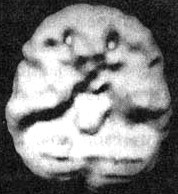

Мозг Кента. СДВ. До и во время приема Adderall

Трехмерное изображение — нижняя поверхность.

При концентрации во время приема Adderall — обратите внимание на улучшившуюся активность в мозге в целом.